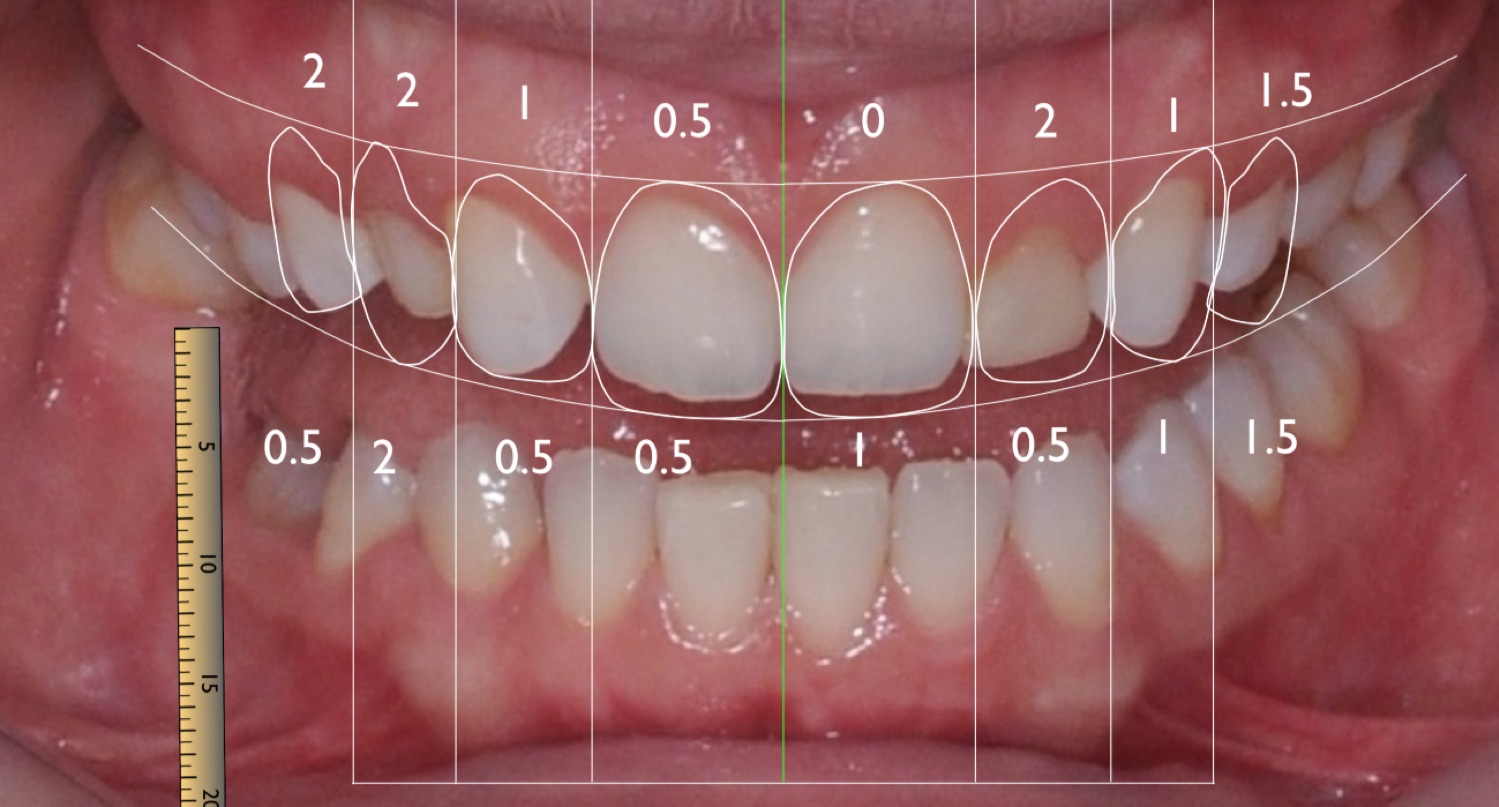

Digital Smile Design (DSD) is a treatment planning protocol that allows for careful analysis of the patient's facial and dental structures through state-of-the-art videography and digital technology.

The entire concept rests on the analysis of the patients’s facial and dental proportions and by incorporating a preselected series of high quality digital photographs and videos into a systematic, effective communicative approach. That supports the evaluation, diagnostic, planning – implementation, of treatment processes.

Today, the DSD Concept is considered the most modern, patient-centered design approach available helping patients recreate their smile.